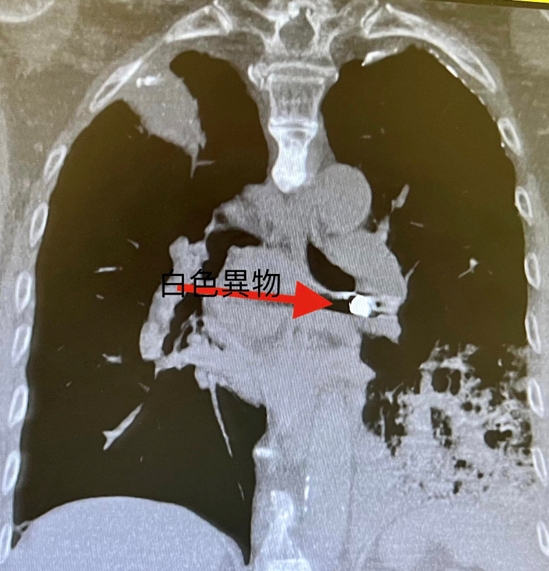

老人應該預防跌倒與嗆到才能延長壽命。 年紀大吞嚥困難常嗆到而不敢吃,產生營養不良。老是嗆入而產生吸入性肺炎而老是要住院治療,以前為了延長壽命減少嗆而接受插鼻胃管進食。但是現在為人性尊嚴與享受美食反對插鼻胃管,所以吸入性肺炎或意外嗆到而死案例增加。年紀大吃東西要小心 常常噎到甚至嗆進呼吸道。因為喉部肌肉萎縮與神經反射遲緩,食道蠕動較差所以導致吞嚥困難且易嗆進呼吸道(大的異物如假牙、骨頭等)而嚴重卡在在大氣管導致猝死。若中小異物卡在支氣管會產生塌陷與阻塞性肺炎,若睡覺口水嗆到至肺泡產生局部發炎,若是多次嗆至肺泡多次發炎產生肺纖維化。 吃東西假牙掉入左下肺支氣管產生阻塞性肺炎案例分享;九十五歲男性有抽煙史產生慢性阻塞性肺病病史且有攝護腺癌病史。最近因吃東西嗆到產生劇烈咳嗽與呼吸困難,且發現假牙不見了來院求診:胸部低劑量電腦斷層顧示右下肺有異物與阻塞牲肺炎(見圖)。緊急支氣管鏡檢並移出此異物。